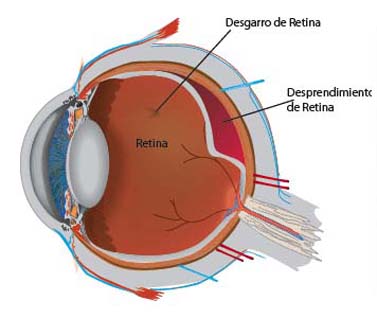

¿Por qué se considera un problema grave un desgarro en la Retina?

Cuando se produce un desgarro en la retina, el líquido situado en la cavidad vítrea puede pasar a través del desgarro y situarse bajo la retina; poco a poco, el líquido del vítreo pasa a través del desgarro retiniano y se instala debajo de la retina, separándola de la pared posterior del ojo. Esta separación, se denomina desprendimiento de retina y la visión se pierde en el lugar en que la retina se desprende.

Puesto que la mayoría de desgarros se localizan en la retina periférica (o parte lateral de la Retina), el desprendimiento produce en primer lugar pérdida de la visión lateral o periférica. Un paciente puede apreciar una sombra oscura o un velo que procede de un lado, de arriba o de abajo. En la mayoría de los casos, después del comienzo de un desprendimiento, toda la retina se desprenderá finalmente y se perderá toda la visión útil de ese ojo.

Diagrama Desprendimiento de Retina

Retinografía, Desprendimiento de Retina